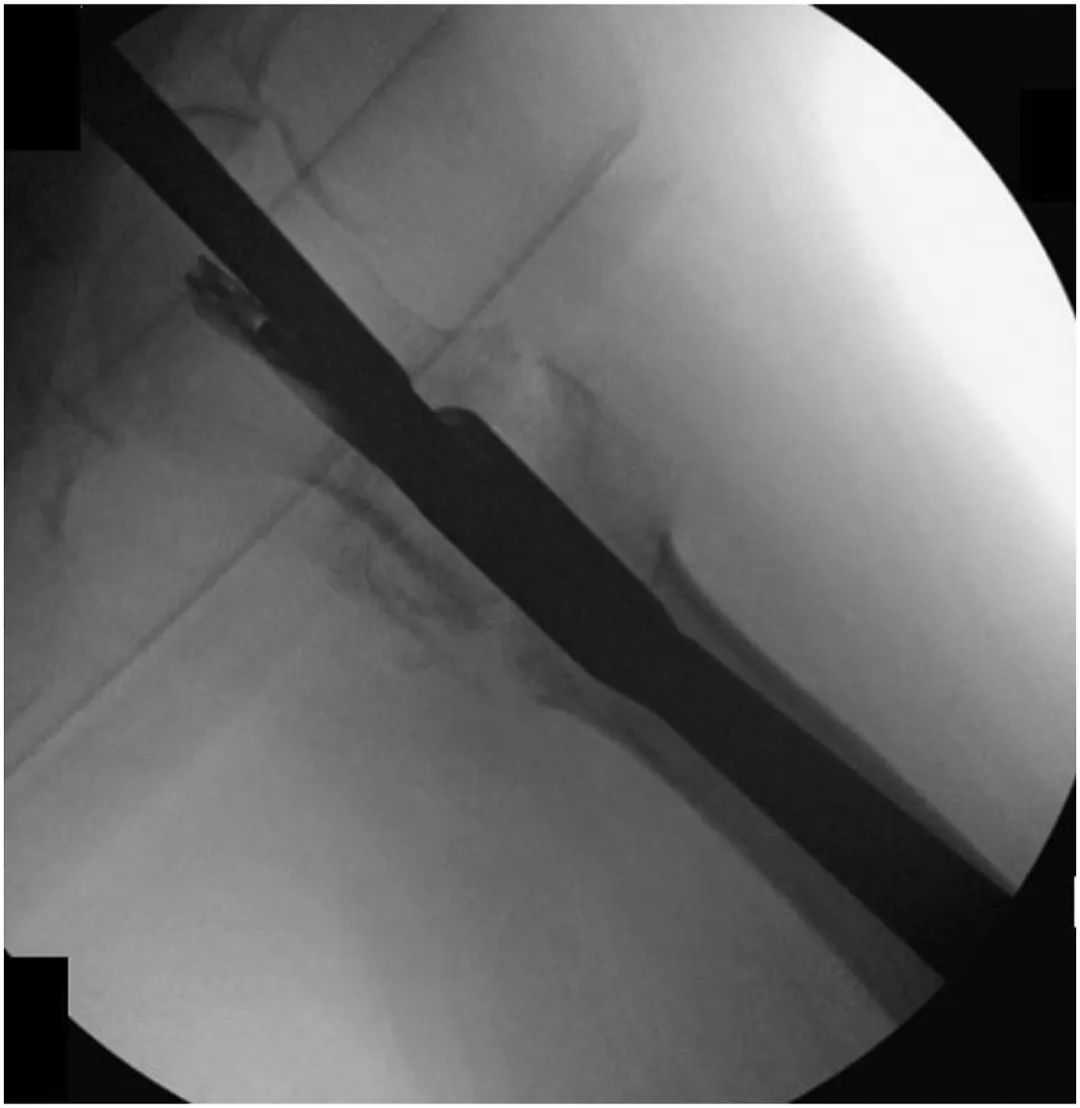

Pour les patients recevant une fixation initiale avec CMN, nous avons effectué un remplacement de clou de tête modifié et un renforcement de ciment osseux.Initialement, une incision de 5 cm a été pratiquée sur le côté proximal du grand trochanter, un fil de guidage a été placé dans le côté proximal du clou et tout l'os a été retiré du côté proximal du clou à l'aide d'un alésoir ouvert.Ensuite, un tournevis hexagonal a été utilisé pour desserrer la vis de fixation en haut du CMN (Figure 2).

Figure 2, fluoroscopie peropératoire montrant un tournevis hexagonal engageant et desserrant une vis de réglage préalablement clouée.